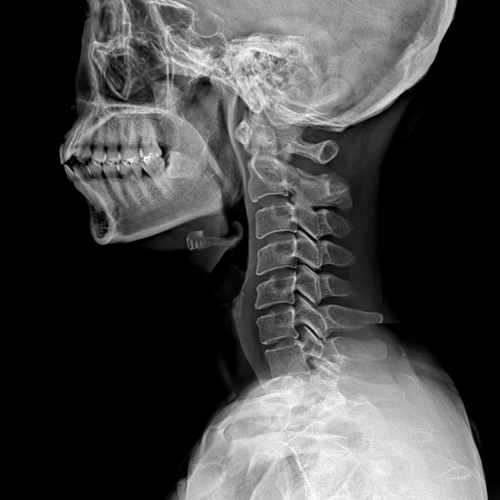

목디스크는 의사의 진찰 소견이 중요합니다.

단순 방사선 촬영은 목 디스크를 보다 강력하게 의심하는 방법은 되지만 확진은 어렵습니다.

근전도 검사가 의료 보험 적용이 되는 디스크 확진 방법이며, MRI는 영상으로 목 디스크가 뒤로 밀린 것을 확인할 수 있습니다.